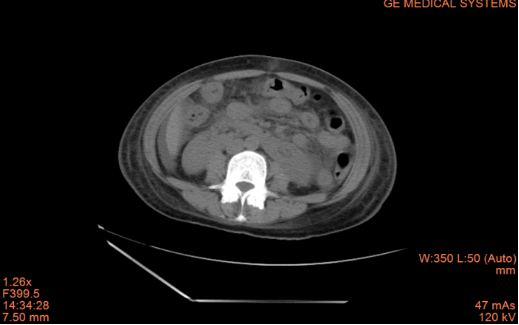

治疗后:

患者小范2月前因腹痛、呕吐在外科住院,诊断肠梗阻,予抗炎、通便治疗后症状好转出院,1月前再次出现反复腹痛、呕吐,CT平扫+增强提示肠壁水肿、增厚,呈“靶征”,胸腔、腹腔、盆腔大量积液。请风湿免疫结缔组织病科汤艳华主任会诊后,发现患者双手掌面多发痛性结节,完善相关免疫检查,发现抗核抗体阳性,dsDNA 阳性,补体下降,诊断系统性红斑狼疮、狼疮肠系膜血管炎转入风湿结缔组织病科。予大剂量激素冲击+免疫抑制剂+抗凝、抑酸等治疗后,症状完全缓解,并可以顺利进食。